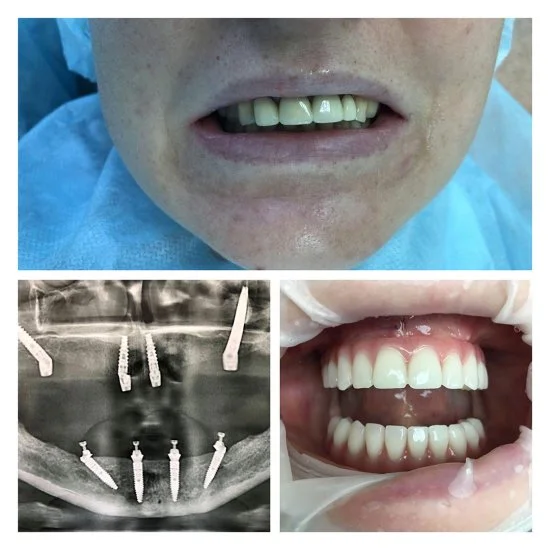

Andrey to doświadczony chirurg stomatolog z ponad 24-letnim stażem. Zajmuje się usuwaniem zębów i implantacją także w trudnych przypadkach — nawet wtedy, gdy inni lekarze nie podejmują się leczenia. Dzięki wiedzy i praktyce potrafi przeprowadzić skomplikowane zabiegi tak, żeby efekt był pewny i przewidywalny.